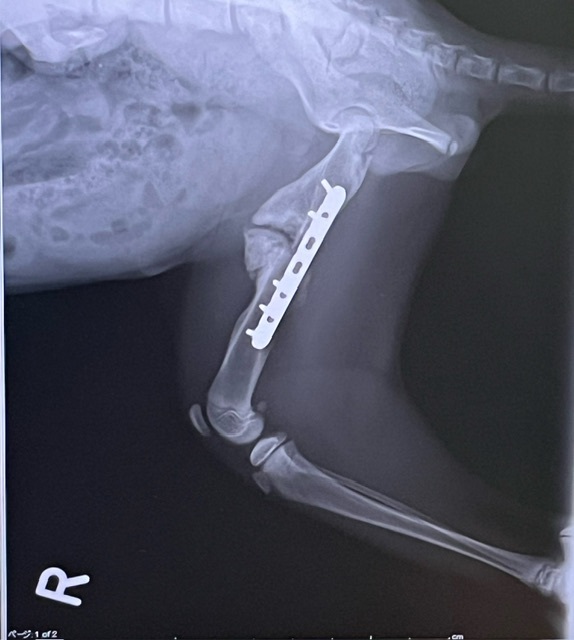

本日、手術後の検診でした。

いつも通りレントゲンで経過観察。

骨折部分も徐々に修復してきています。

※膨らんでいる部分は段々元に戻るそうです。

順調そうで安心しました😊